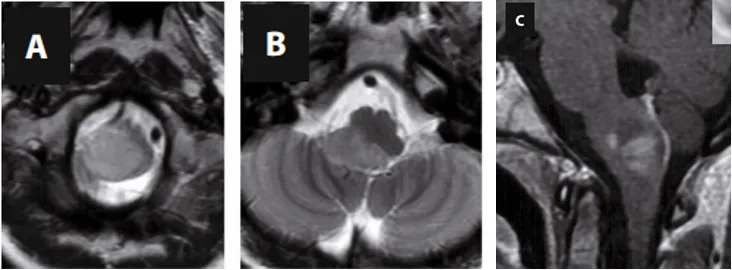

术前MRI(A-C)

延髓下部髓内发现了一个大型肿瘤,并已延伸至右侧小脑下脚。

原来,这个生长在生命中枢(脑干)区域的肿瘤,正是导致她长期顽固性呃逆的“罪魁祸首”。它持续刺激或压迫了控制打嗝反射的神经通路,导致了这场漫长的折磨。

面对这个位于手术“禁区”的复杂病变,INC的巴特朗菲教授为安妮制定了精密的手术方案。他主刀施行了后正中入路肿瘤切除术,并在持续术中神经电生理监测的全程护航下,精准操作,顺利切除了肿瘤,解决了安妮打嗝的这一罪魁祸首。术后影像证实了肿瘤的满意切除。